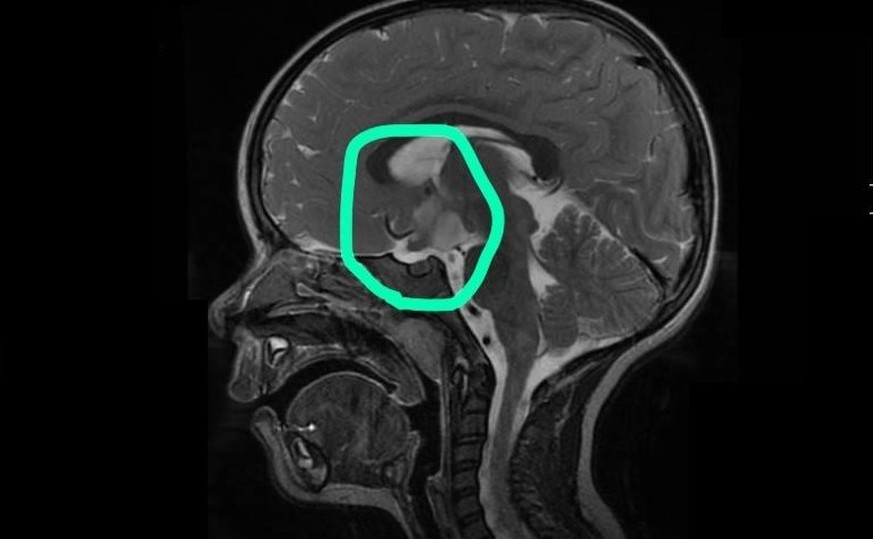

Les parents ne souhaitent pas voir la situation de Lisa se dégrader davantage et acceptent. L'IRM livre aussitôt une constatation: une tumeur de la taille d’une balle de golf se trouve dans la tête de Lisa.

La tumeur exerce une pression sur l'hypothalamus, ce qui fait que Lisa ne ressent plus la faim. La tumeur exerce également une pression sur le chiasma optique, le carrefour des nerfs optiques. Si la tumeur continue à se développer, Lisa risque de perdre la vue.

Le problème: la tumeur se trouve au milieu du cerveau et ne peut donc pas être enlevée chirurgicalement. Une intervention causerait trop de dégâts.

La tumeur ne cesse pas seulement de croître, elle rétrécit même. «Nous avons eu une chance énorme que Lisa réagisse aussi bien à la thérapie», dit Sascha. Après 18 mois et 72 séances, la thérapie touche à sa fin. La tumeur est certes toujours dans la tête de Lisa, mais dans le meilleur des cas, elle reste désormais à cette taille. Elle «sommeille» — comme le dit Sascha à sa fille.